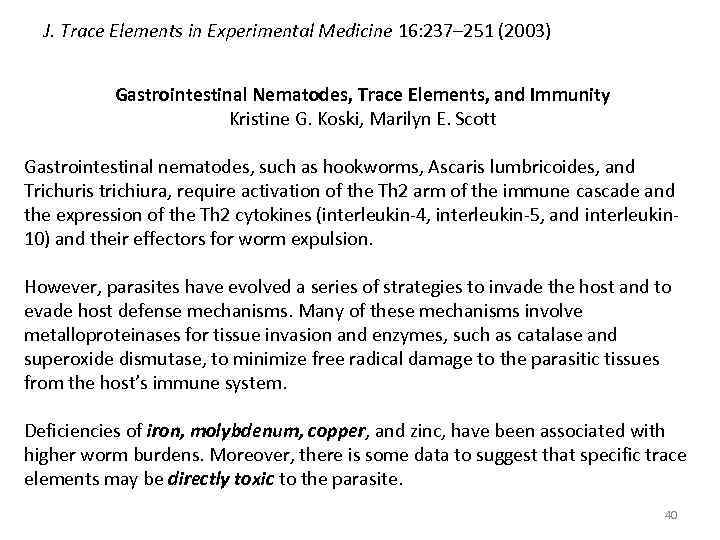

J. Trace Elements in Experimental Medicine 16: 237– 251 (2003) Gastrointestinal Nematodes, Trace Elements, and Immunity Kristine G. Koski, Marilyn E. Scott Gastrointestinal nematodes, such as hookworms, Ascaris lumbricoides, and Trichuris trichiura, require activation of the Th 2 arm of the immune cascade and the expression of the Th 2 cytokines (interleukin-4, interleukin-5, and interleukin 10) and their effectors for worm expulsion. However, parasites have evolved a series of strategies to invade the host and to evade host defense mechanisms. Many of these mechanisms involve metalloproteinases for tissue invasion and enzymes, such as catalase and superoxide dismutase, to minimize free radical damage to the parasitic tissues from the host’s immune system. Deficiencies of iron, molybdenum, copper, and zinc, have been associated with higher worm burdens. Moreover, there is some data to suggest that specific trace elements may be directly toxic to the parasite. 40